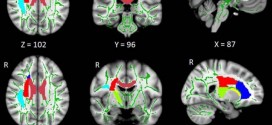

MRI Scans Link Insomnia To Abnormalities In Brain’s Communication Networks. Doctors have long known that people who suffer from insomnia are at risk of depression, anxiety and mood problems. Using a sophisticated MRI technique, researchers have found abnormalities in the brain’s white matter tracts in patients with insomnia. Results of the study were published online in the journal Radiology.